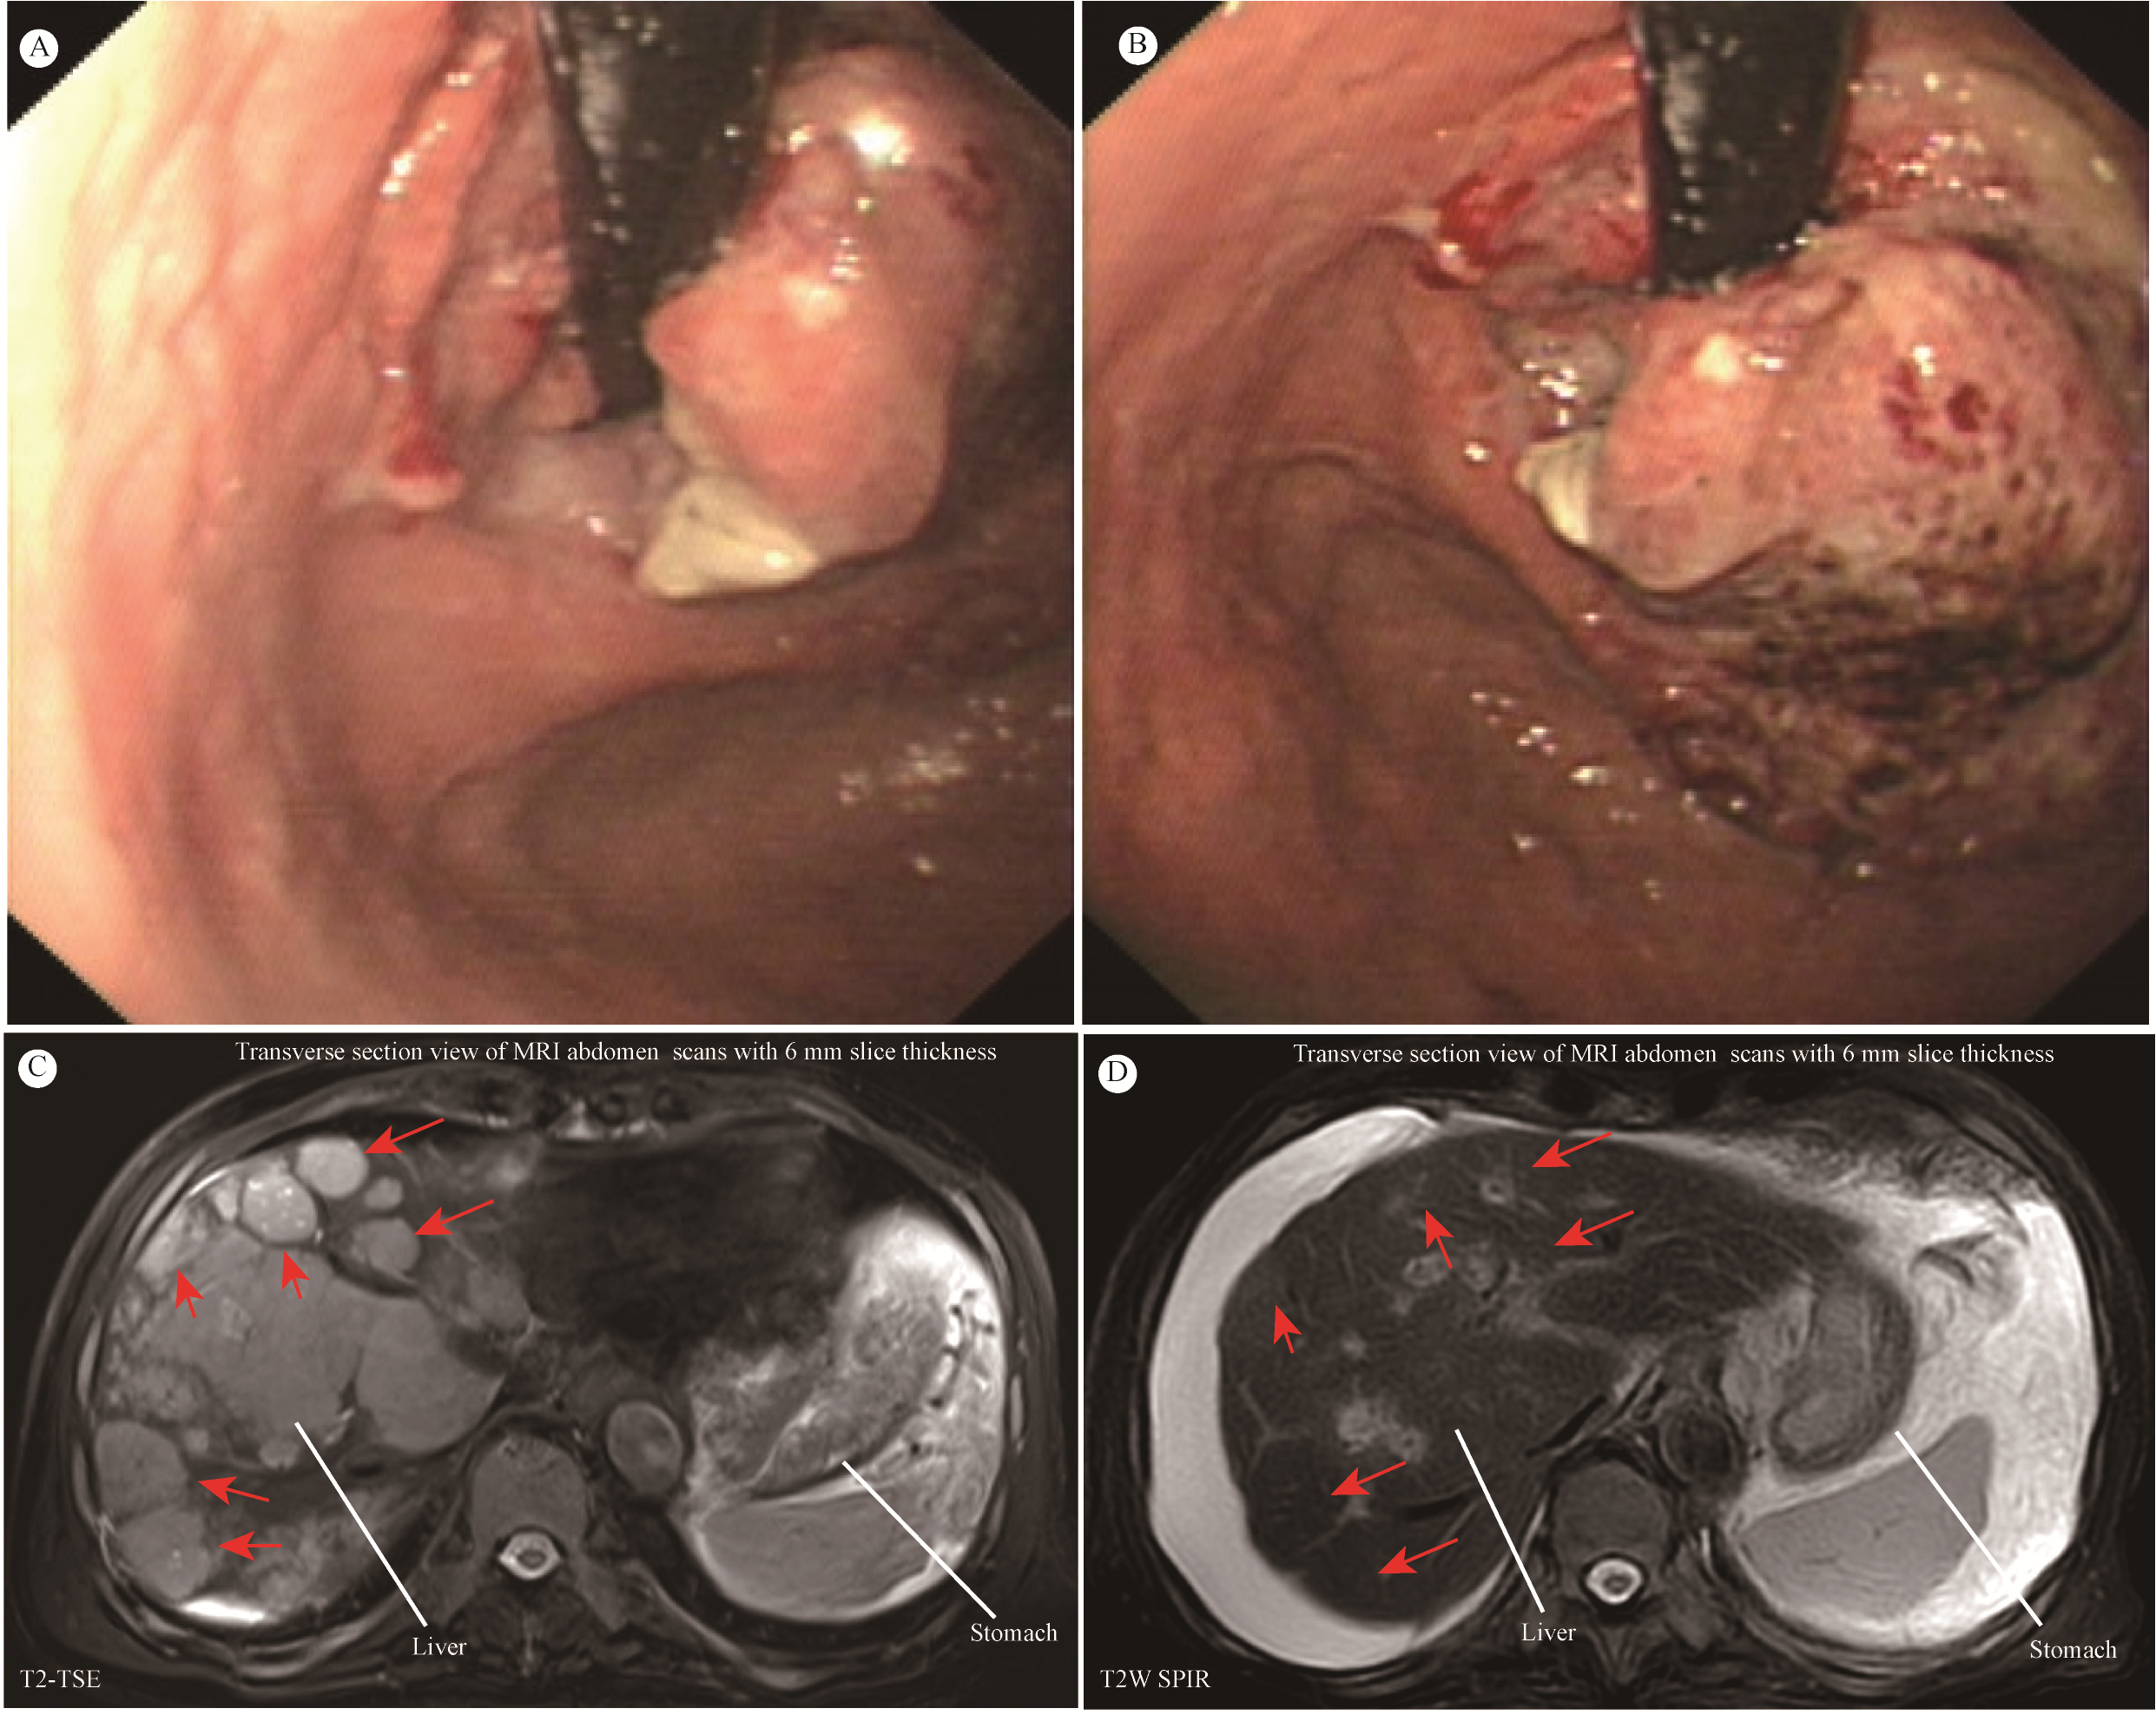

The patient, an 81-year-old male, underwent gastroscopy on April 7, 2024, which showed an irregular tumor on the lesser curvature and posterior wall of the gastric fundus. The tumor occupied about one-third of the gastric fundus area, presenting with ulceration, hardening, and active bleeding (Figures 1A, B). Enhanced abdominal MRI showed thickening of the gastric wall and multiple hepatic masses (Figure 1C). The pathology of the gastric biopsy revealed atypical cell infiltration, indicating a malignant tumor with two components: one part was moderately differentiated adenocarcinoma, while the other component exhibited a solid pattern of poorly differentiated carcinoma with strong neuroendocrine marker expression, suggesting large cell neuroendocrine carcinoma. Immunohistochemistry results were as follows: Adenocarcinoma component: CK8/18(+), CK7(+), Syn(-), EMA(+), Hepatocyte(-), Ki-67(40%+), Her2(1+), MLH1(+), PMS2(+), MSH2(+), MSH6(+), P53(80%+, mutated); Poorly differentiated carcinoma component: CK8/18(+), CK7(-), Syn(strong+), EMA(-), Hepatocyte(-), Ki-67(50%+), Her2(1+), MLH1(+), PMS2(+), MSH2(+), MSH6(+), P53(80%+, mutated); PD-L1(BP6099, TC score: 5%+). The diagnosis was stage IV gastric cancer with multiple hepatic metastases. Considering the patient’s advanced age, history of diabetes, coronary artery disease, chronic kidney disease, and poor liver and kidney function, nivolumab (240 mg q2w) monotherapy was initiated on April 9, 2024. After more than four months of monotherapy with nivolumab, contrast-enhanced MRI imaging demonstrates significant interval regression of multiple hepatic metastases and a substantial reduction in portal vein thrombus burden compared with prior examinations. Improved visualization of the middle and left hepatic veins is noted. The gastric wall exhibits mild thickening, which represents a mild improvement relative to previous findings. Furthermore, the mass at the gastric fundus demonstrates an interval reduction in size (Figure 1D).

Figure 1

(A, B) Giant space-occupying lesion at the gastric fundus. (C, D) MRI of the abdomen. Contrast-enhanced MRI of the abdomen showed that the size and number of multiple liver metastatic tumor lesions have notably shrunk after more than four months of monotherapy with nivolumab (red arrow).